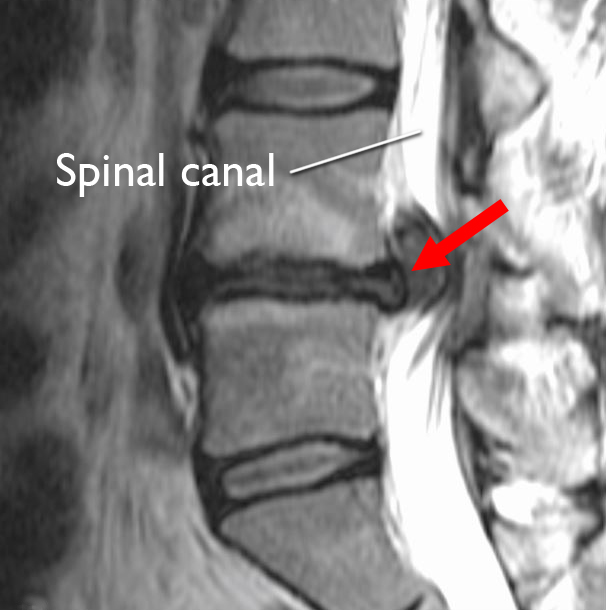

Magnetic resonance imaging (MRI) scan. MRI scans provide clear images of the body's soft tissues, including intervertebral disks. Your doctor may order an MRI scan to help confirm the diagnosis and to learn more about which spinal nerves are affected.

MRI of herniated disk

MRI scan shows a herniated disk in the lower back (arrow). The disk is bulging out toward the spinal canal, putting pressure on the spinal cord and nerve roots.

Reproduced from Truumees E, Prather H (eds): Orthopaedic Knowledge Update 5. Rosemont, IL. American Academy of Orthopaedic Surgeons, 2017, pp. 243-251.